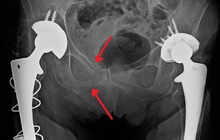

Surgery

Surgery is often required for pelvic fractures. Many methods of pelvic stabilization are used including external fixation or internal fixation and traction.[7][8] There are often other injuries associated with a pelvic fracture so the type of surgery involved must be thoroughly planned.[9]